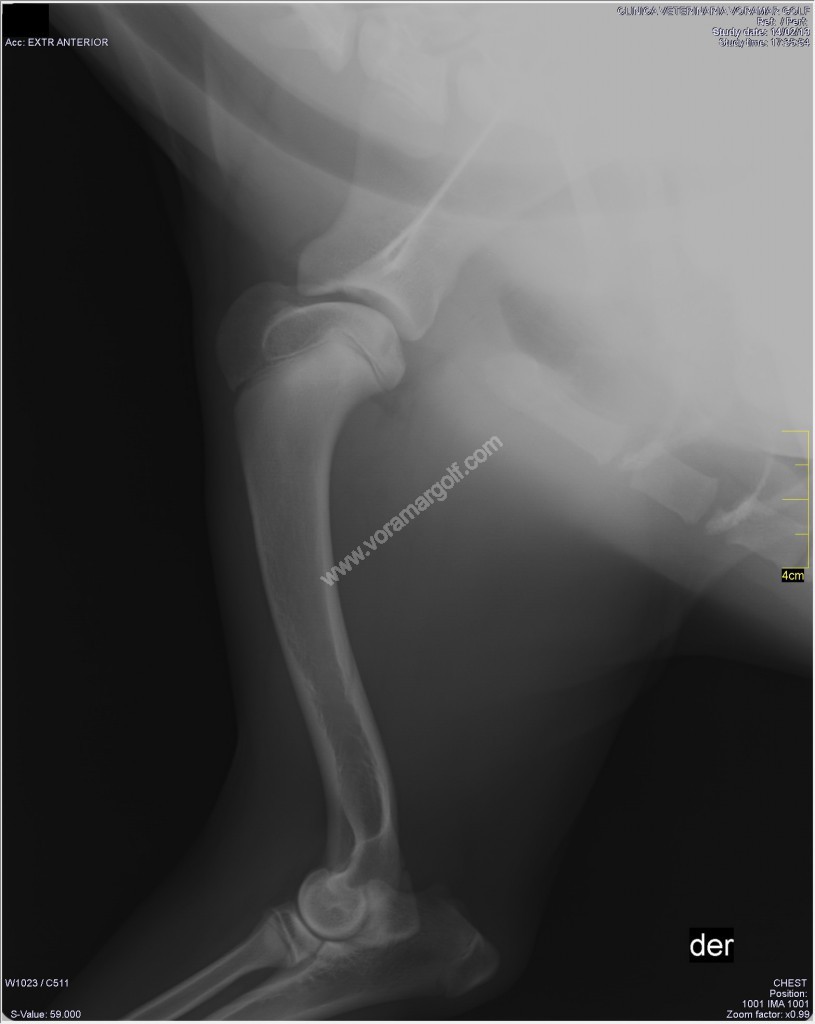

WebDislocaciones de hombro por lo general implican lágrimas en los ligamentos o los músculos del manguito de los rotadores que sujetan el hombro al hueso húmero . Mientras que los. WebLa dislocación de la articulación del hombro, también llamada luxación, es una lesión paralizante y dolorosa que puede afectar a perros de cualquier tamaño o raza. Los. WebLa cirugía consiste en estabilizar la articulación del hombro que los médicos logran mediante el uso de una banda de piel para asegurar la articulación del hombro al. WebDislocación articular en perros. El hueso actúa como el marco arquitectónico del cuerpo en todos los mamíferos. Es una estructura rígida que ayuda a mantener la forma del cuerpo. WebMétodo 2Venda el hombro de tu perro si presenta fractura. 1. Asegúrate de que la fractura sea en el hombro. Siempre debes acudir al veterinario para que revise la lesión, pero. WebDescripción general. Un hombro dislocado es una lesión en la que el hueso del brazo superior se sale de la cavidad ahuecada que forma parte del omóplato. El. WebLa dislocación del hombro en los perros es una condición donde la articulación del hombro del perro (articulación glenohumeral) se luxa o se subluxa. La articulación del hombro es. WebInicio Consejos veterinarios Primeros auxilios Dislocaciones o huesos rotos. El resultado de una caída, accidente o movimiento brusco puede ser una dislocación o ruptura de. WebQUE ES LA OCD o OSTEOCONDRITIS DISECANTE DEL HOMBRO. La ostecondritis es una enfermedad del desarrollo del perro que afecta a los cartílagos de.

Veamos PPT - Radiología del Perro: miembro torácico PowerPoint Presentation más